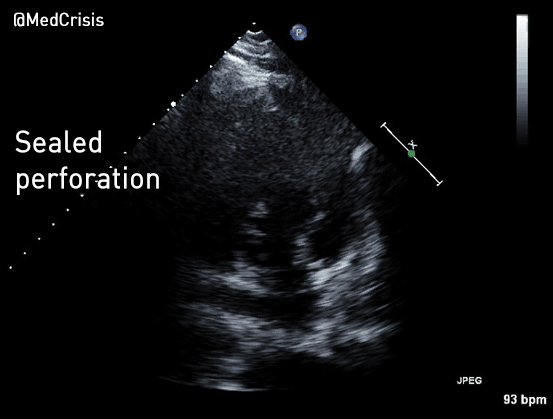

Apical 2 chamber. This view demonstrates the bulging from the RV also appears to involve the LV. This is a sealed perforation with aneurysm formation.

In this remarkable loop, the echo probe moves and one can clearly appreciate the defect in the septum, along with the thin membranes sealing the perforation.

This patient suffered both a large VSD and a sealed perforation of the inferobasal free wall.